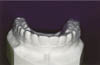

Custom-made positioners are fabricated on articulated models in which teeth from both arches have been sectioned from the models, realigned and waxed in an ideal configuration. This incorporates minor corrections in tooth position and occlusal relationship. The elastomeric or rubber material is then formed around the teeth and the coronal portion of the gingiva (Fig. 2).

Figure 2

Click to see the larger image

Fig 2: Custom fabricated positioner.